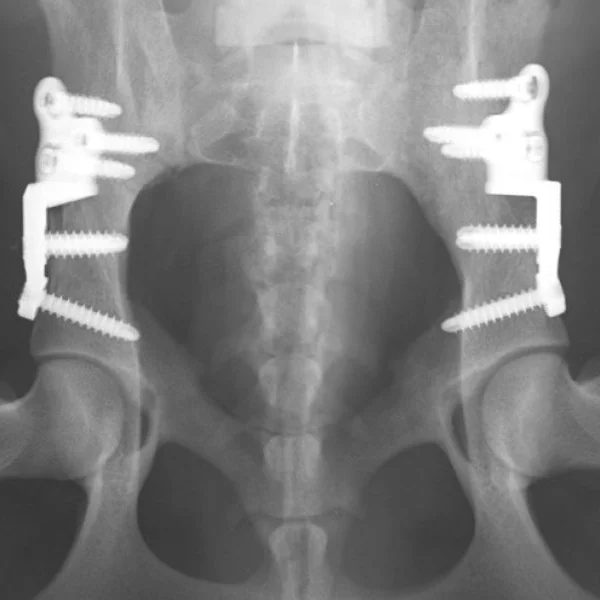

KYON ALPS® DPO – Double Pelvic Osteotomy

Double Pelvic Osteotomy (DPO) is performed on puppies with femoral head subluxation due to increased dorsal acetabular rim slope and/or excessive joint laxity. The purpose of DPO is to arrest the development of Hip Dysplasia (HD) in the early stage of the disease.

The ALPS DPO is based on ALPS Technology and is an integral part of the ALPS® Product Range.

Pre-contoured plate to best match the DPO construct and bases on the principles of ALPS® Technology, which aim to minimize the contact-area of the plates with the periosteum and minimize vascular damage

Immediate and safe fixation. Dedicated compression hole and locking screws fixation for immediate stability of the implant. The screw direction is fixed to maximize construct stability and avoid articular surfaces and the osteotomy.

Reduced risk of infection. Integrates the technological features and biological benefits of the ALPS® Technology into the DPO technique.

Superior biocompatibility. Titanium alloy is noted for biocompatibility.

The ALPS® DPO plate was developed in close collaboration with Dr. Aldo Vezzoni and went through several iterations to ensure safety and effectiveness of the implant.

DPO modifies the direction of the forces inside the joint, redirecting the femoral head inside the acetabulum. Pelvis geometry and width are not affected and dedicated DPO implants are designed for a stable construct.